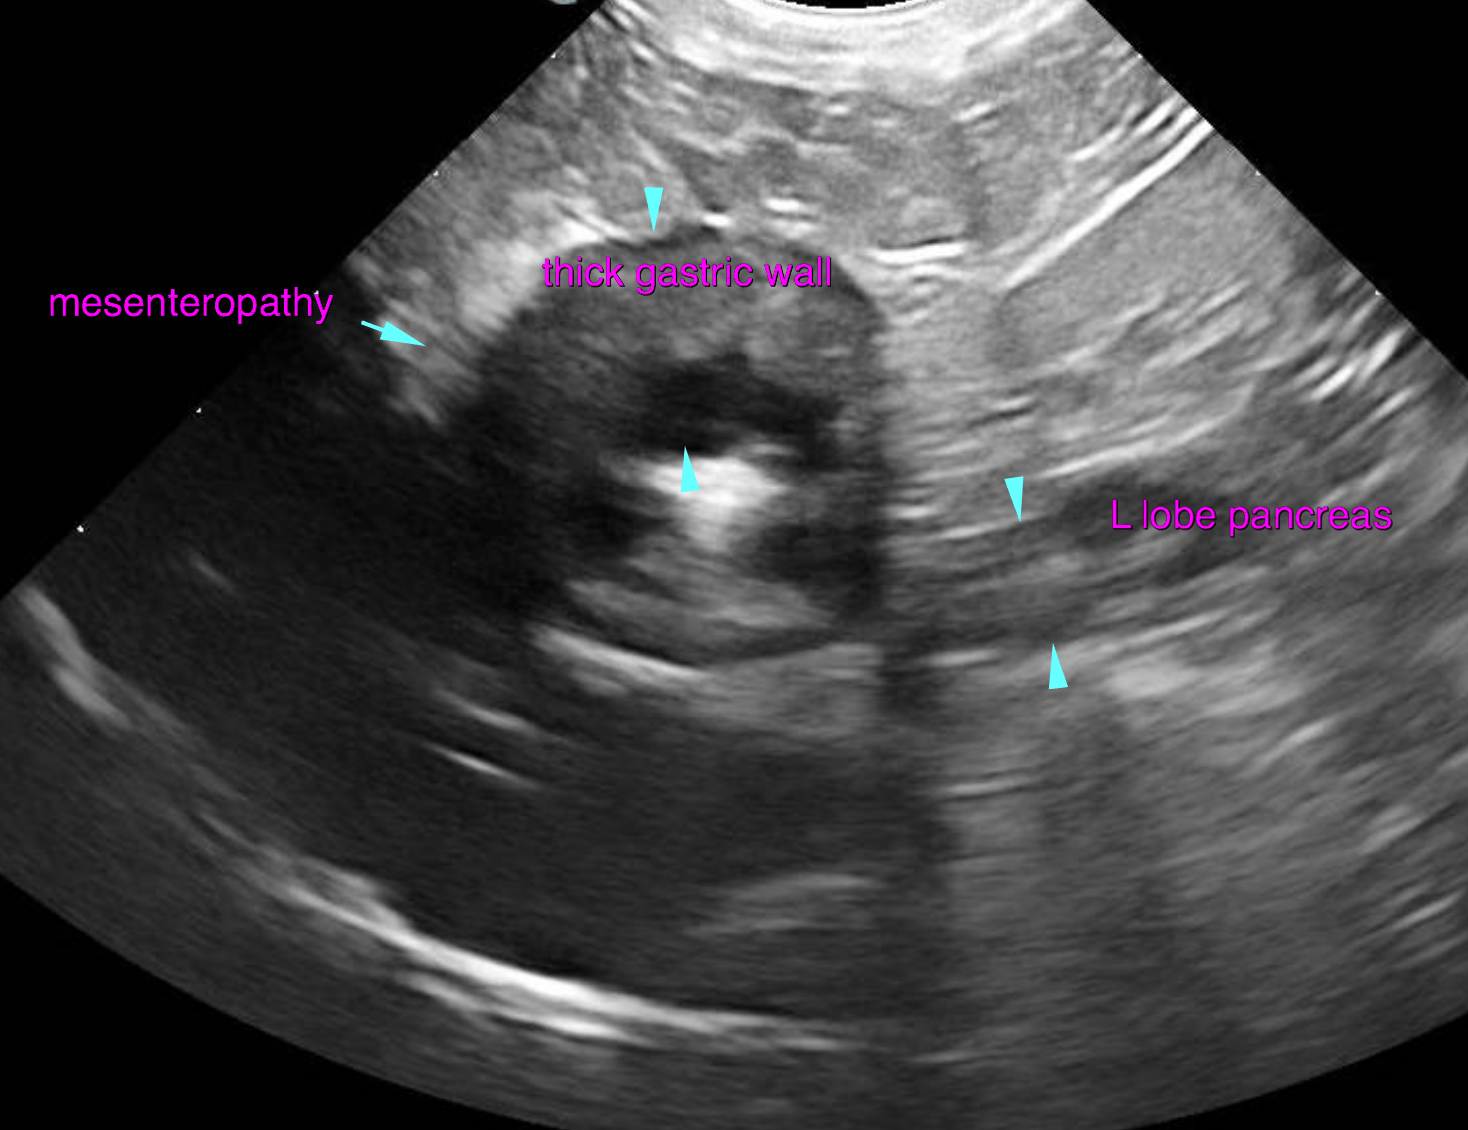

The left and right lobe of the pancreas are embedded in a slightly hyperechoic mesentery, but within normal limits for size, shape and echoarchitecture.  The gastric wall presents moderate generalized wall thickening emphasizing the submucosal layer. The interrugal wall thickness is up to 5 mm. The wall layering is moderately obscured. The mucosal surface is slightly irregular. A moderate amount of fluid is present within the stomach. The surrounding mesentery is mildly increased in echogenicity with slightly ill defined echotexture. The stomach is hypomotile. The duodenum is slightly dilated with fluid, presents hypermotility and mucosal fogging. The wall layering is witho normal limits. The jejunum presents similar changes as the duodenum. There is no obstructive pattern of the digestive tract.